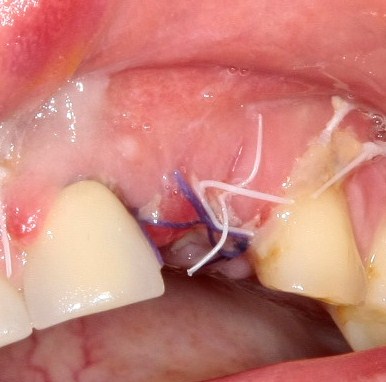

Если вы когда-нибудь видели подобные операции, то наверняка обращали внимание на порядок действий — сначала устанавливаются имплантаты, затем укладывается графт и только потом фиксируется мягкотканный аутотрансплантат. Для удобства в этом и похожих клинических ситуациях мы поменяли порядок действий:

Сначала мы провели и зафиксировали деэпителизированный соединительнотканный аутотрансплантат (ССТ). Для этого мы сформировали тоннель и использовали ортодонтическую проволоку в качестве проводника. Подробнее об этой методике можно почитать здесь>>.

Затем уложили ксенографт. Особенностями Bio-Oss Collagen являются удобство адаптации, устойчивость к вымыванию и выдавливанию, поэтому мы просто уложили полученные ранее пирамидки вестибулярно относительно будущего имплантата, после чего прижали их с помощью уже упоминавшихся аналогов имплантата, входящих в хирургический набор имплантационной системы Xive (кстати, при работе с другими имплантационными системами для паковки графта в лунке можно использовать круглые остеотомы для синуслифтинга).

В совокупности, аугментация лунок перед установкой имплантатов занимает около 20 минут — и это самый долгий из всех хирургических этапов лечения.